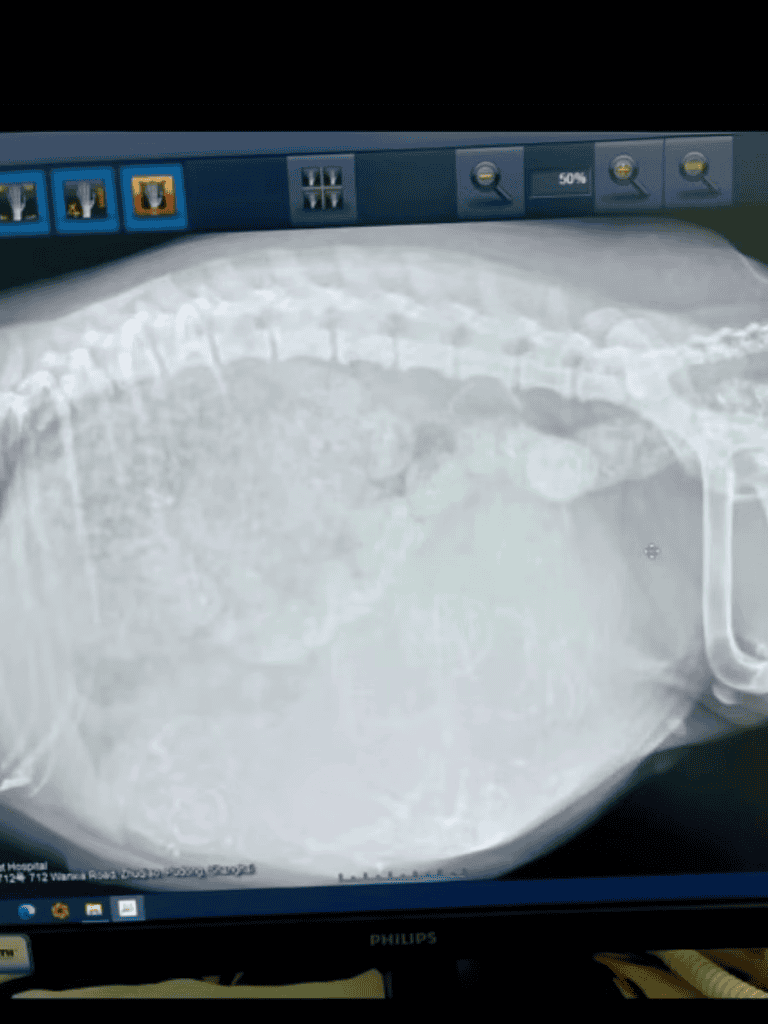

The family tenderly tended to her wounds and provided a cozy spot where she could rest and feel secure. At the first light of dawn, they whisked her off to the vet, who revealed the heartening news: she was expecting a litter of seven puppies.

The vet explained the situation. The dog was pregnant with seven puppies and malnourished. Her body struggled to nourish the litter.

Upon noticing her significantly swollen belly, they understood that she was on the verge of giving birth.